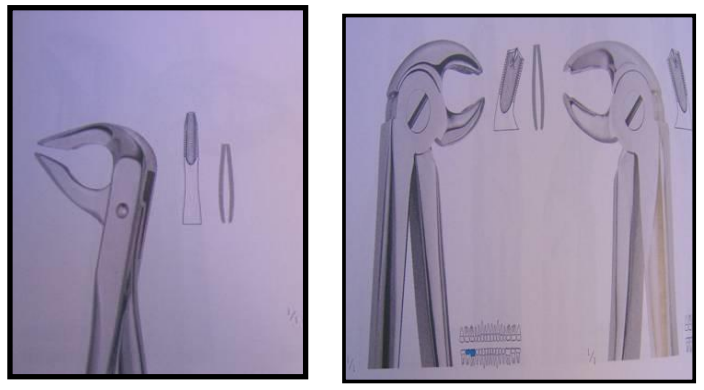

Instrumentation : le Davier

Description

Un davier est formé de trois parties :

- Mors : Partie travaillante, permettant de saisir la dent grâce à leur forme adaptée à la morphologie dentaire.

- Branches : Généralement symétriques, légèrement courbées.

- Charnière : Point d’union des deux bras de l’instrument.

Variétés

Au niveau mandibulaire

Les mors forment un angle droit avec les manches.

- Daviers pour incisives et canines.

- Daviers pour prémolaires.

- Daviers pour 1re et 2e molaires.

- Daviers pour dents de sagesse.

- Daviers pour racines.

Technique d’utilisation

Paramètres généraux

- Écarter les parties molles (lèvres, joues, langue).

- Le davier doit saisir fermement la couronne de la dent et être aligné dans son axe.

- Maintenir les tables osseuses entre le pouce et l’index pour éviter les fractures.

- Travailler calmement pour éviter le dérapage des instruments.

Au niveau mandibulaire

- Bloc incisivo-canin et prémolaire :

- Mouvements de rotation et vestibulaire.

- Traction vers le haut.

- Bloc molaire :

- Molaire droite : Praticien en position derrière et latérale par rapport au patient.

- Molaire gauche : Praticien en face du patient.

- Mouvements vestibulaires.

- Dents de sagesse : Mouvements vestibulaires accentués.